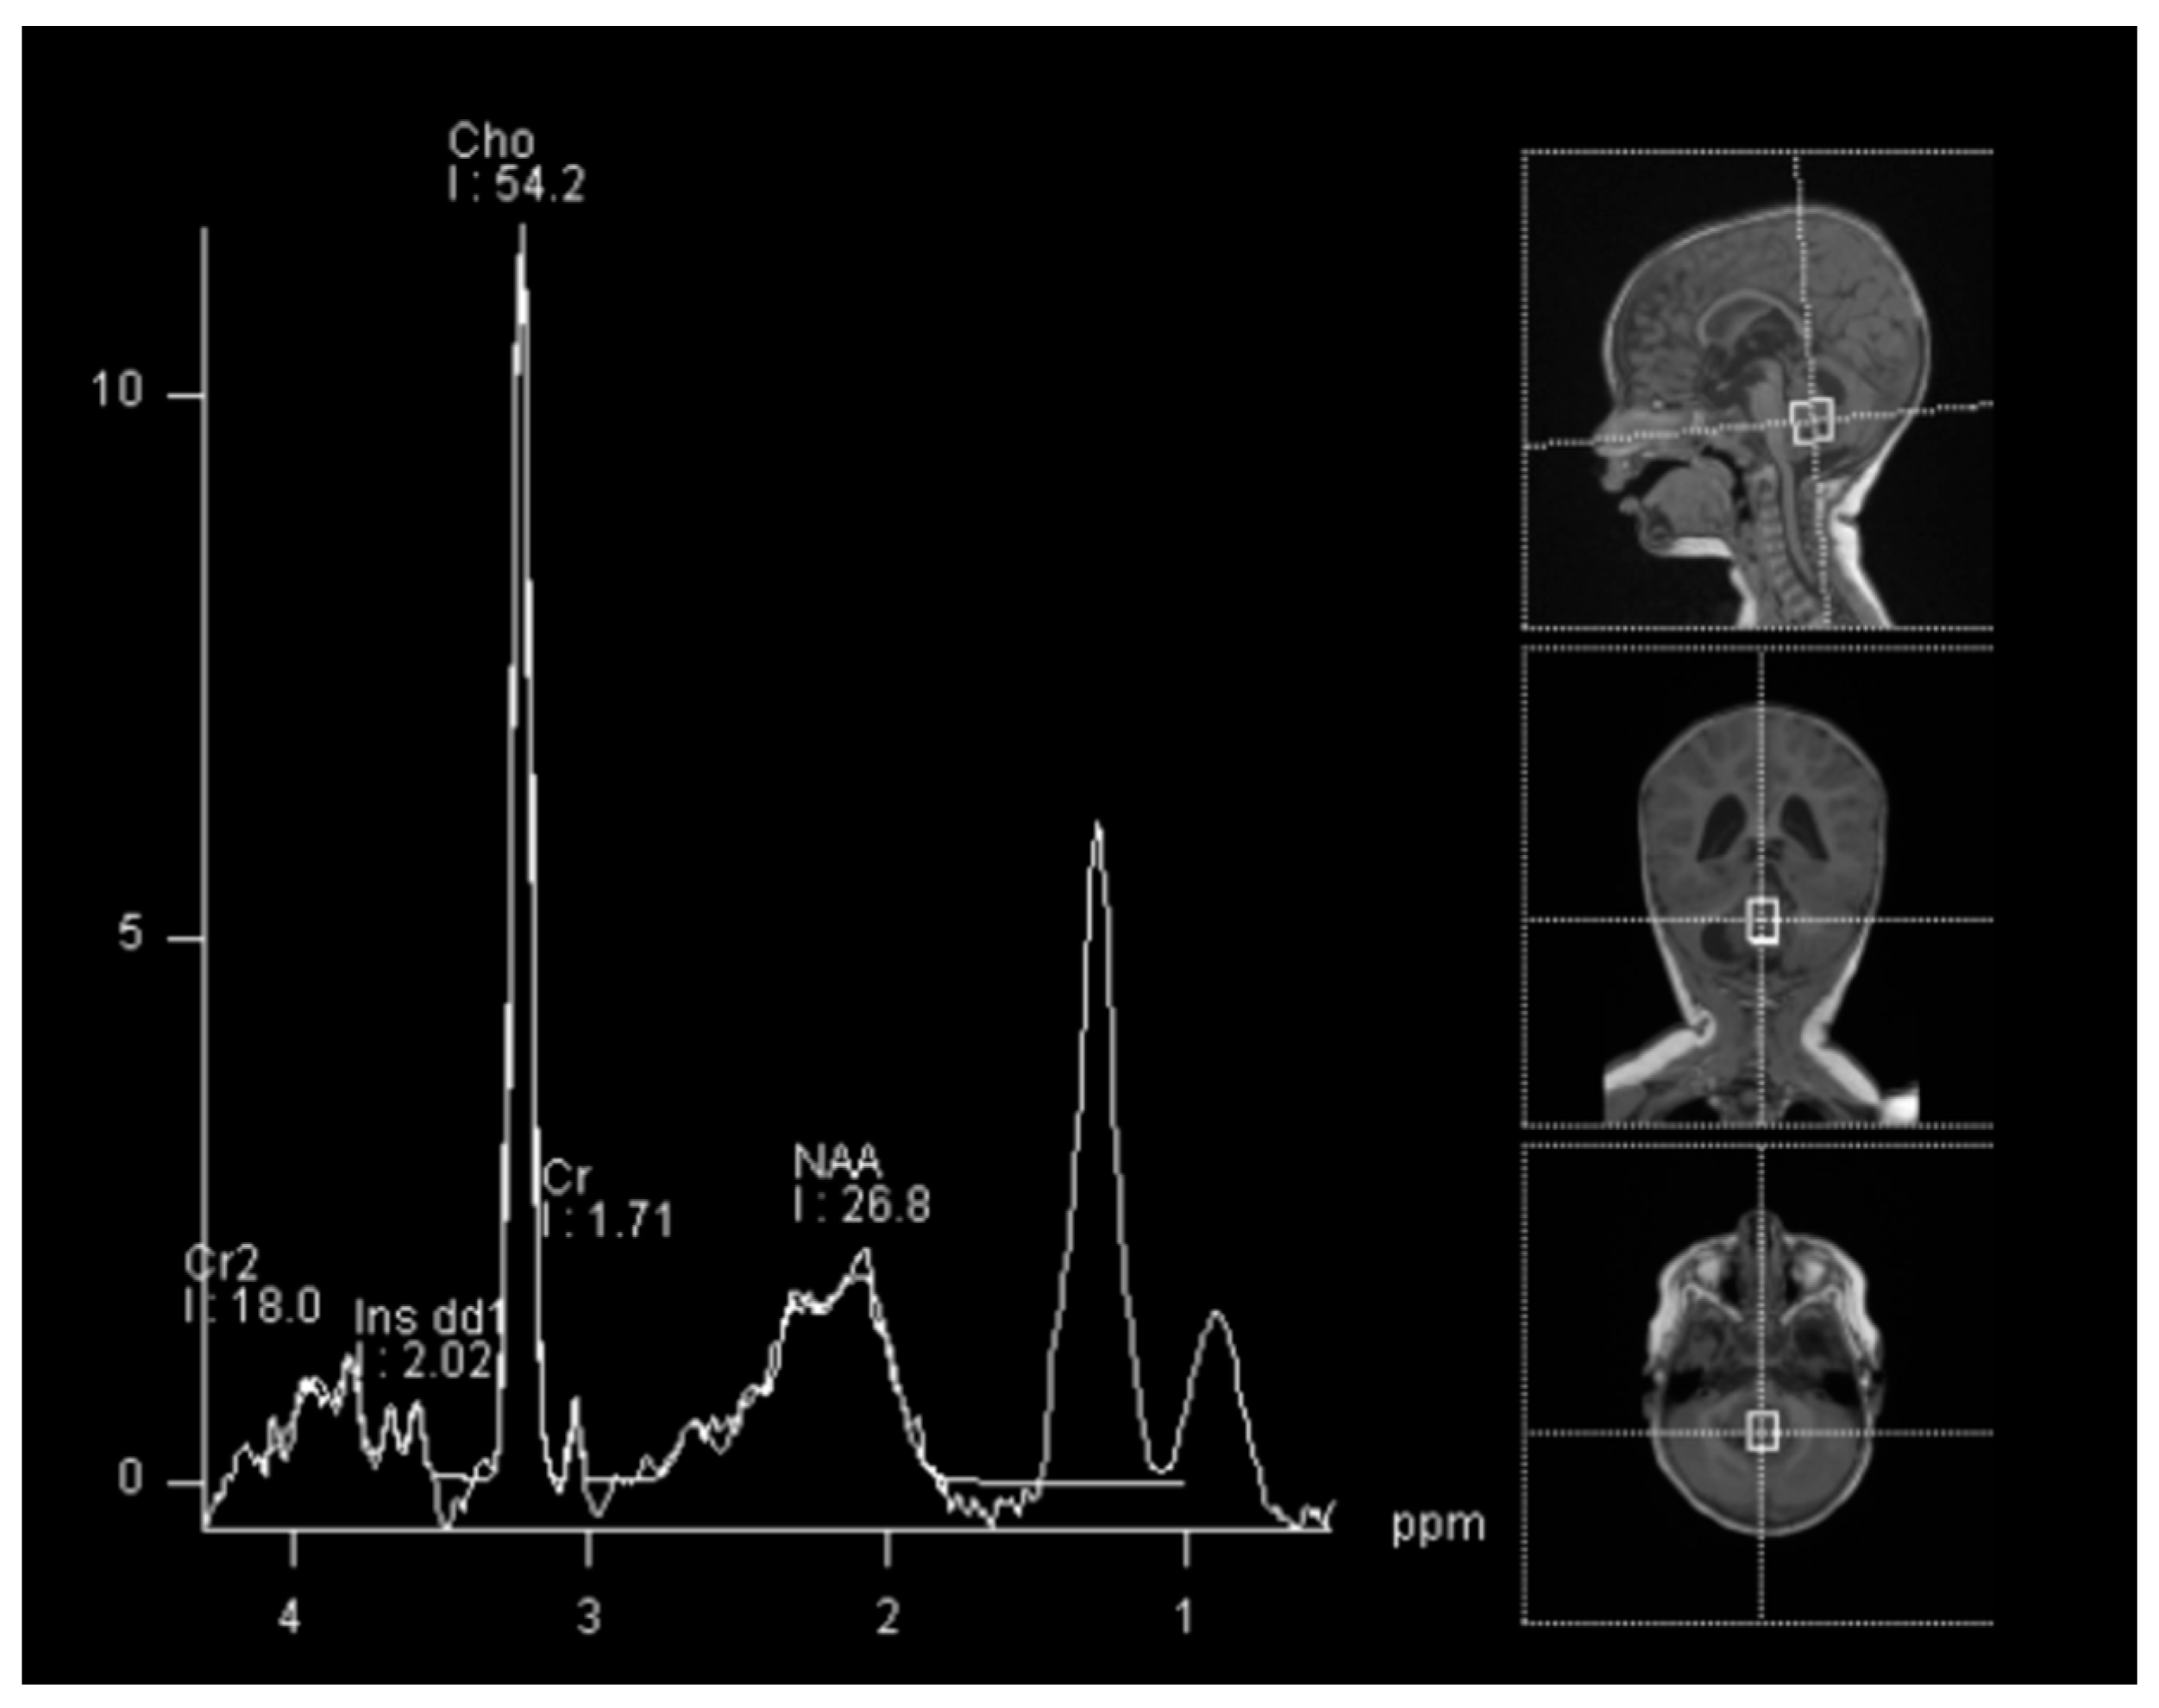

In spectroscopy sequences an elevated choline peak and low N-Acetylaspartate (NAA) and creatine, were found, suggesting an ATRT (Figure 3). No leptomeningeal dissemination was found.

Figure 3.

Spectroscopy analysis showing an augmented rate of choline, in favor of a malignant lesion.